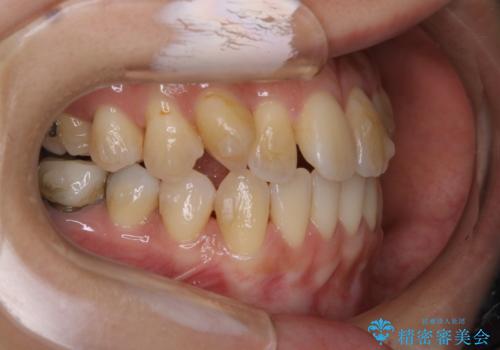

前歯が内側に入っている:インビザライン治療

- 上の前歯は内側に入っていることが気になりご相談にいらした方です。インビザラインにて治療を行いました。

1週間でのマウスピース交換を指示していましたが、20時間以上使えない時があると不安との事で、2週間ごとの交換にしていました(実際はほとんど20時間以上使用できていたようです)。治療終了まで時間はかかりましたが、最終的に綺麗に並べることができ、大変喜んでいただけました。